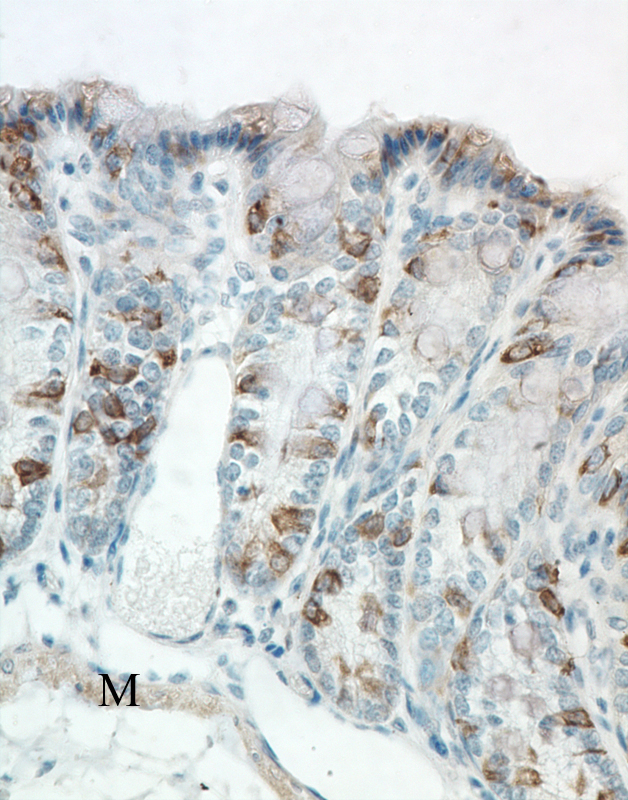

Colon - Normal tissue. Individual epithelial cells of colonic glands are strongly labeled for alpha-catenin. Smooth muscle fibers of the muscularis mucosa show moderate diffuse cytoplasmic labeling for alpha-catenin.

Large intestine, colon -Normal tissue.

IHC for alpha catenin